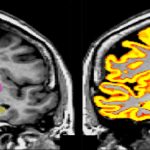

First brain scans available from worlds largest imaging study

LONDON: UK Biobank is obtaining a rich set of brain scans from thousands of participants,… read more